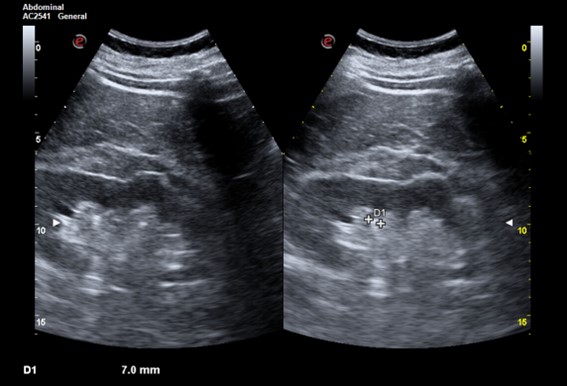

Descripción de los hallazgos ecográficos y las imágenes más relevantes para la resolución del caso.